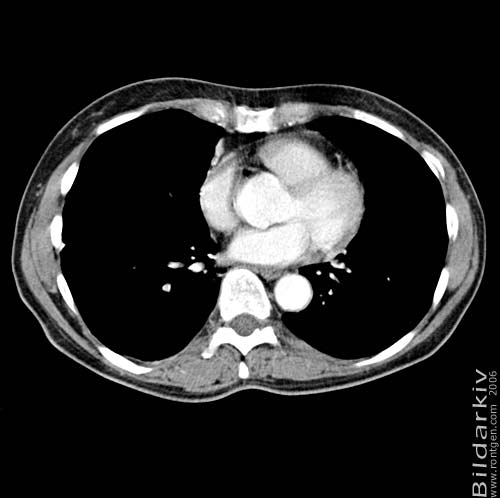

Thorax 38

Snitt över thorax med kontrast. Sk. mediastinum-fönstersättning.

CT Röntgen Helsingborgs lasarett

Mediastinum